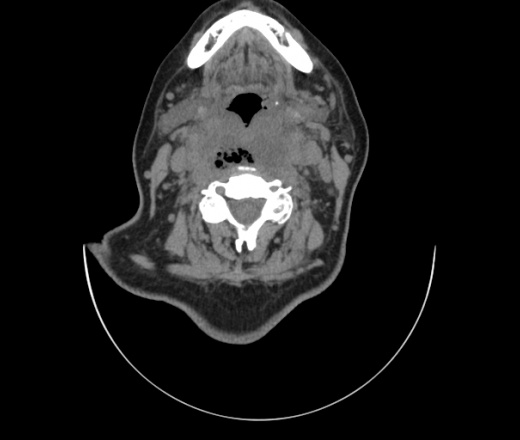

Женщина поступила в х/о спустя 4 дня после того как при употреблении карася подавилась костью.

Наличие газа в средостении на протяжении тел С2-С6 (медиастинальна эмфизема); рыбная кость на уровне тела С6.

При всем уважении, но говорить о медиастинальной эмфиземе, оценивая мягкие ткани шеи, как-то слишком резко. На мой взгляд, это ретрофарингеальное пространство.

Эвакуировали почти 100мл гноя. Но кость не смогли найти. Думаю что она даст дальнейшее ослоднение. Эндоскопически за черпалонадгортаной звязкой не смогли зайти в пищевод, все мягкие ткани отечные, просвет пищевода сдавлен. По всей видимости параэзофагеальная клетчака тоже задействована. Эмпиема, если ее можно так назвать, незнаю как правильно дошла до уровня яремной вырезки. Чем закончиться напишу. Ждем медиастинита.

Флегмона заглоточного пространства шеи, только операция, флегмоны вскрывают. Риск медиастинита.

Согласен с Вами; конечно, наличие газа в клетчатке ретрофарингеального пространства (затмение с опечаткой..). К сожалению, процесс "продвигается" к медиастиниту. Но почему никто, не отмечает наличие рыб. кости; или это для Всех очевидно?

Так вы уже отметили. Хотя ориентировал бы не скелетотопически, а на перстнечерпаловидный сустав.

Кость то мы сразу выявили, размеры где то 17*2мм, но ее так и не получается найти в этой каше